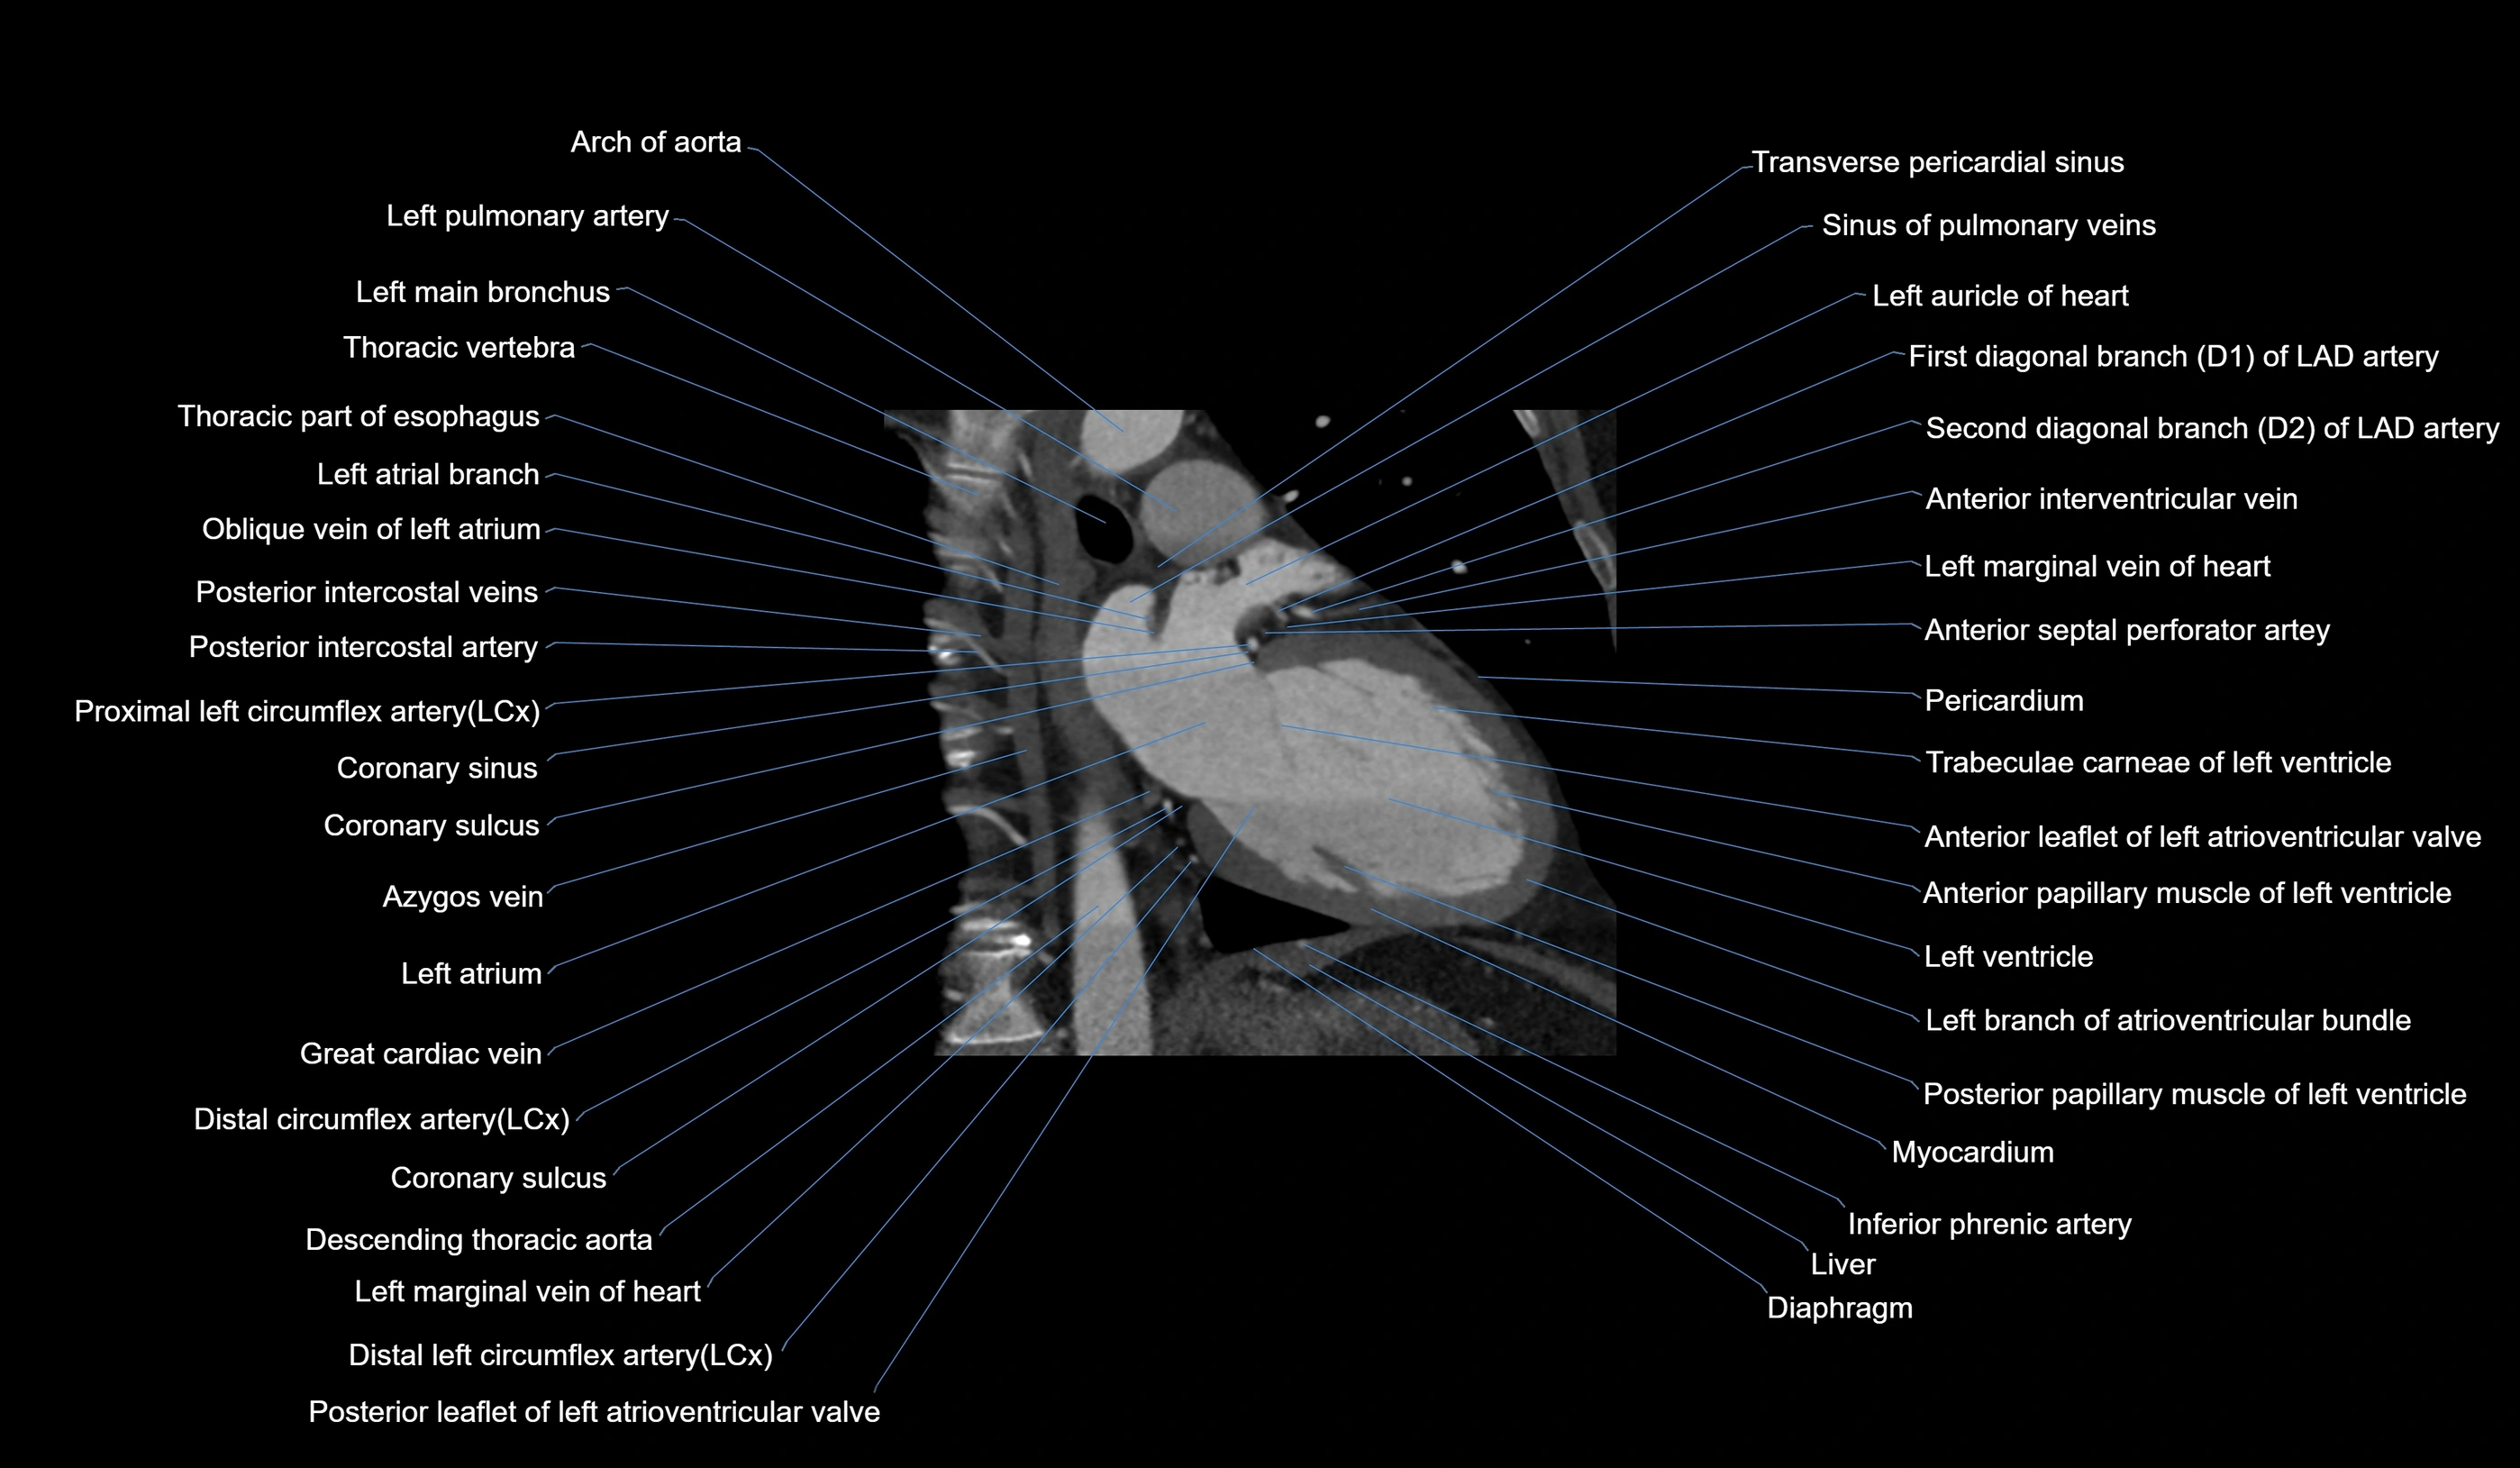

- Arch of aorta

- Left pulmonary artery

- Left main bronchus

- Descending thoracic aorta

- Left atrial branch (coronary artery)

- Oblique vein of left atrium

- Posterior intercostal veins

- Posterior intercostal arteries

- Circumflex artery (LCx)

- Coronary sinus

- Coronary sulcus

- Great cardiac vein

- Left marginal vein

- Left atrium

- Middle cardiac vein

- First diagonal branch (D1) of LAD

- Second diagonal branch (D2) of LAD

- Anterior interventricular sulcus

- Posterior leaflet of left atrioventricular valve

- Inferior phrenic artery

- Diaphragm